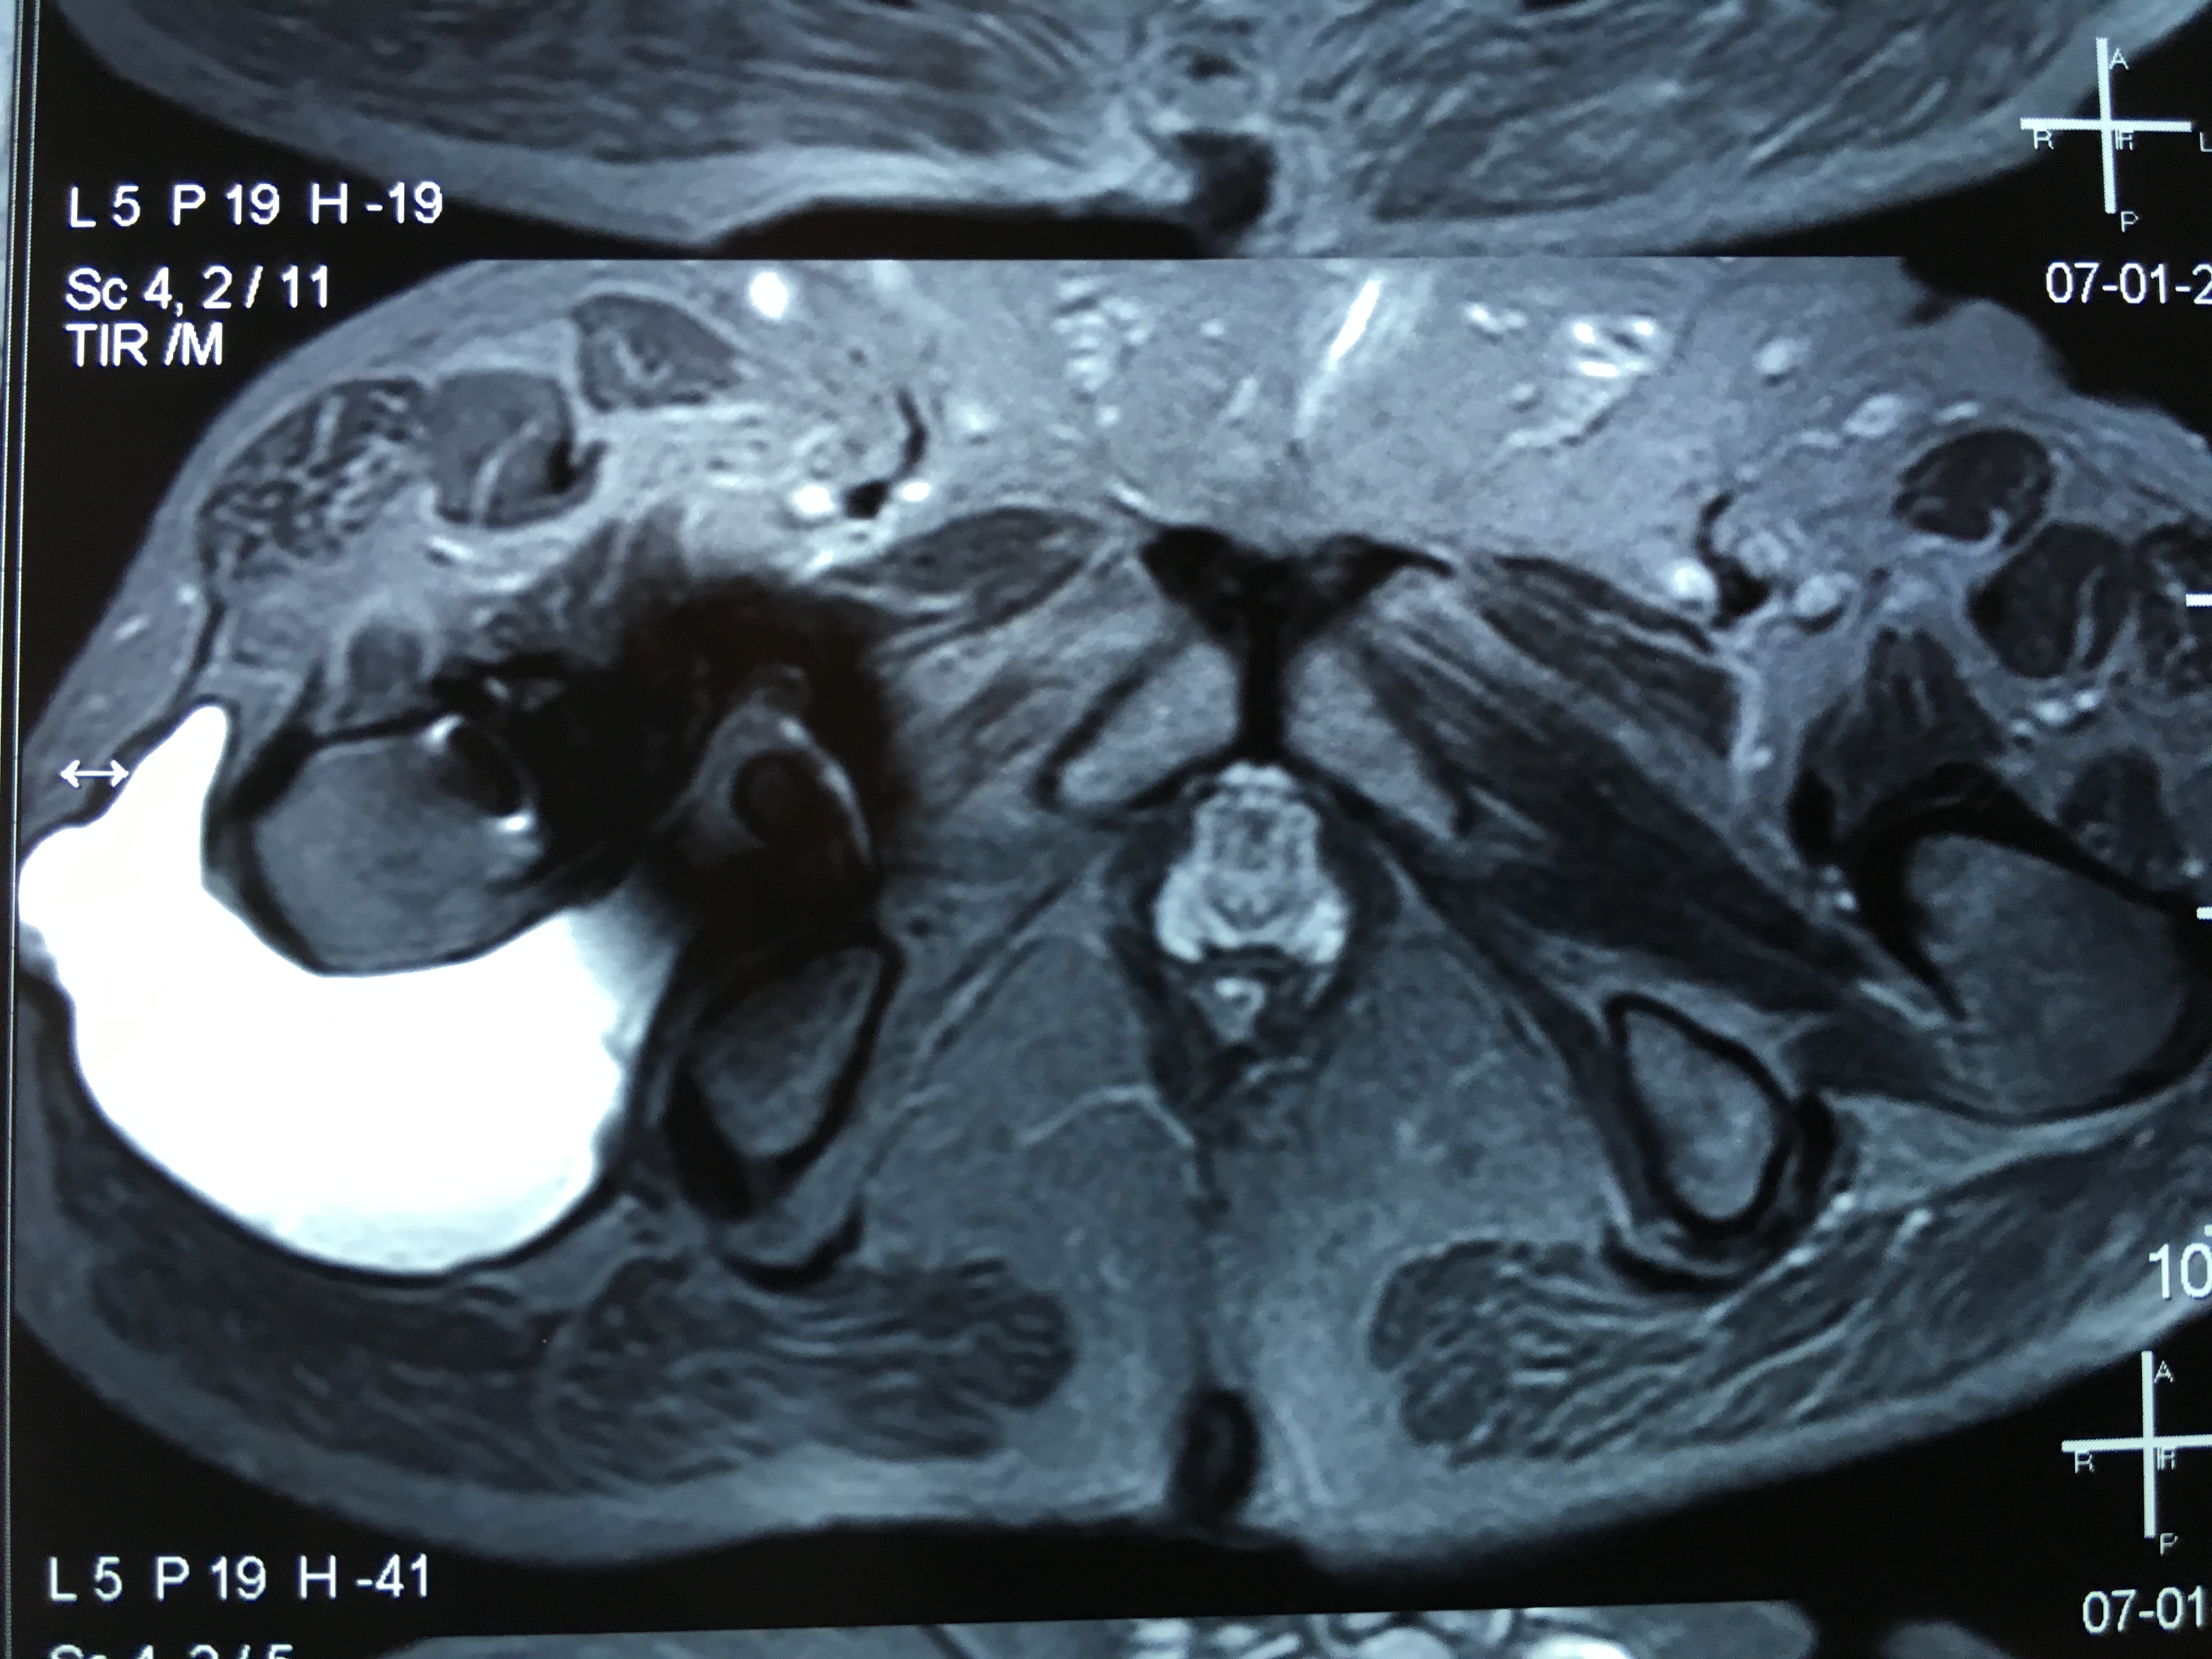

Cotilos de doble movilidad. Uso para la revisión femoral aislada de prótesis de cadera con fricción metal/metal con cabezas grandes. [Use of dual mobility acetabular cups for isolated femoral revision of metal on metal hip resurfacing arthroplasty using larger femoral heads]